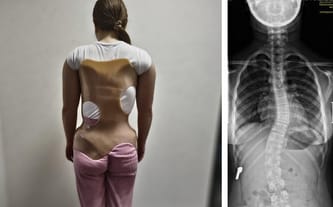

U naszej córeczki zdiagnozowano skoliozę na dwóch odcinkach kręgosłupa (na odcinku lędźwiowym 28° i rotację dwóch kręgów oraz na odcinku piersiowym 29° i rotację jednego kręgu).

W tej chwili Hania nosi gorset ortopedyczny, który zatrzymał pogłębianie wady kręgosłupa. Nosząc go, unika poważnej operacji! Jej jedyną szansą na sprawność i lepszą przyszłość jest bardzo kosztowna rehabilitacja, która mocno obciąża nasze finanse!

Hania na szczęście może chodzić do szkoły, widywać się z rówieśnikami, w miarę "normalnie" funkcjonować. Niestety gorset, który musi nosić 23 godziny na dobę, bardzo utrudnia jej codzienność.